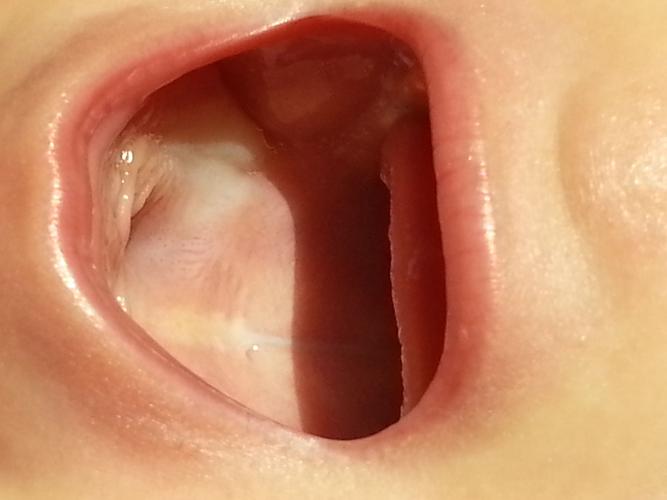

宝宝口腔上颚内壁发白 生理性/正常现象(无需过度担心) 马牙(Epstein pearls) 特征:在宝宝上颚中线附近或牙龈边缘,出现一些白色或黄白色的小颗粒,像米粒或小沙子一样,大小不一,数量可能是一个或多个。 成因:这是胚胎发育时期残留的上皮细胞堆积形成的,是一种正常的生理现象。 处理:完全不需要处理! 这些“马牙”...